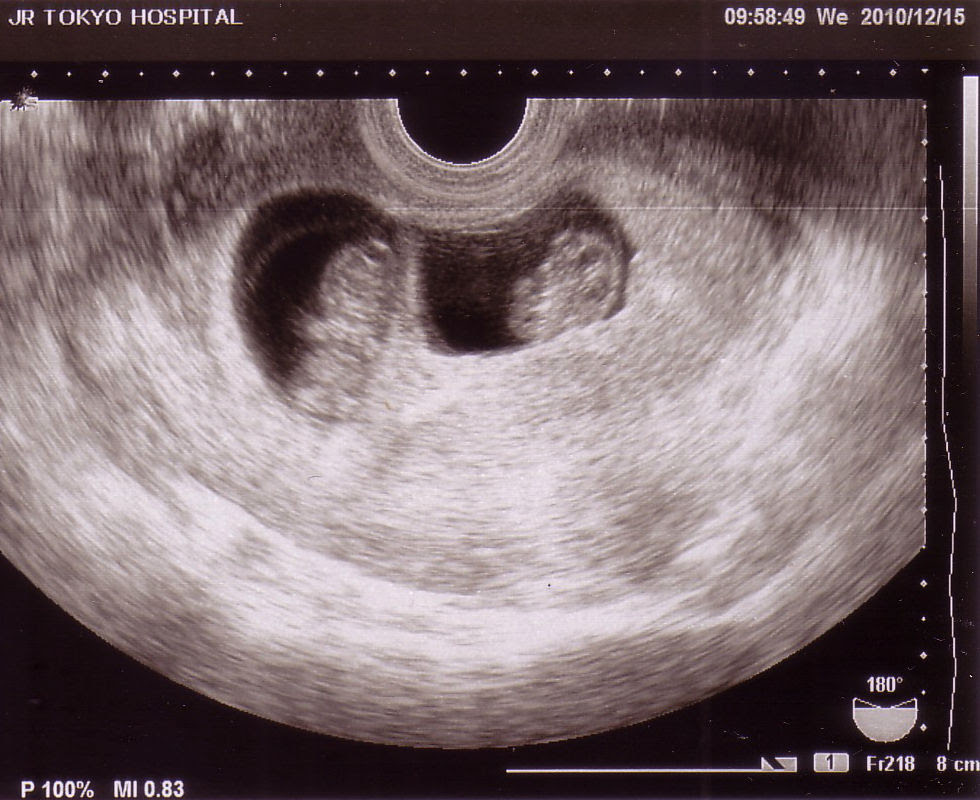

双子のエコー写真

双子のエコー写真-エコー検査で双子かどうかがわかる時期 双子であるかどうか最終的に判断されるのは、妊婦検診でのエコー検査です。エコー検査には経膣検査と経腹検査があります。 経膣エコー検査 子宮口から直接器材を入れて、子宮の中の様子を調べます。双子妊娠13週 エコー検査 クリニックではなく、病院のエコー検査へ。 みかんちゃんは口がパクパクしていて、りんごちゃんは手を振っている感じでした。 これが13週の双子のエコー写真 写真上の方に、りんごちゃんの手が認識できるでしょうか。

双子の9週目のエコー写真 あんまりエコー写真が上手じゃないですよね。。 エコーの機械が古そうだったからか画質もよくないですが、胎嚢が2つ写っているのでかろうじて双子だってわかるエコー写真かな? 双子の13週目のエコー写真二卵性双子のエコー写真5週~29週公開&双子4dエコーの疑問を解決! maybee1013 年11月24日 / 21年1月7日 これ、よく聞かれました。「双子を妊娠した時って、最初から双子って診断されるの?」 「双子を妊娠した時のつわりは、めちゃめちゃ辛いって本当?」 ・・・一卵性双生児を出産した私は、こういう内容の質問を今でも聞かれます。 双子って、何だか興味が湧いて・・・